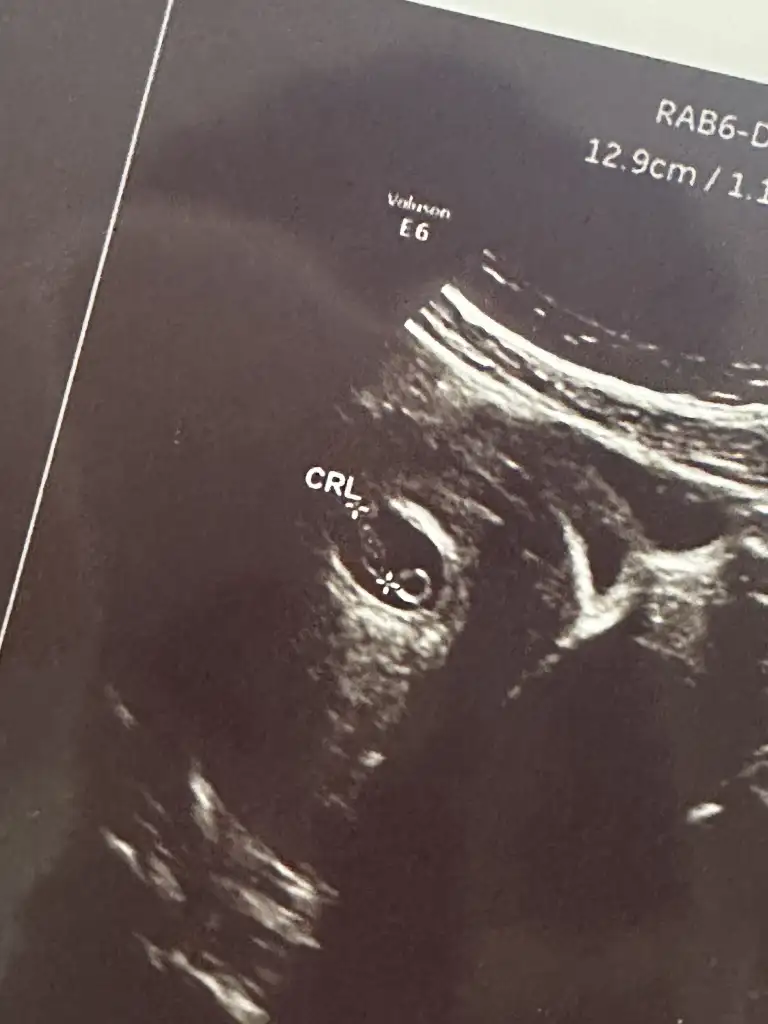

Kızlar benimkinide tahmin edin yaa kese yuvarlakmı ovalmi ben anlamıyorum burda 6+4 😂😂